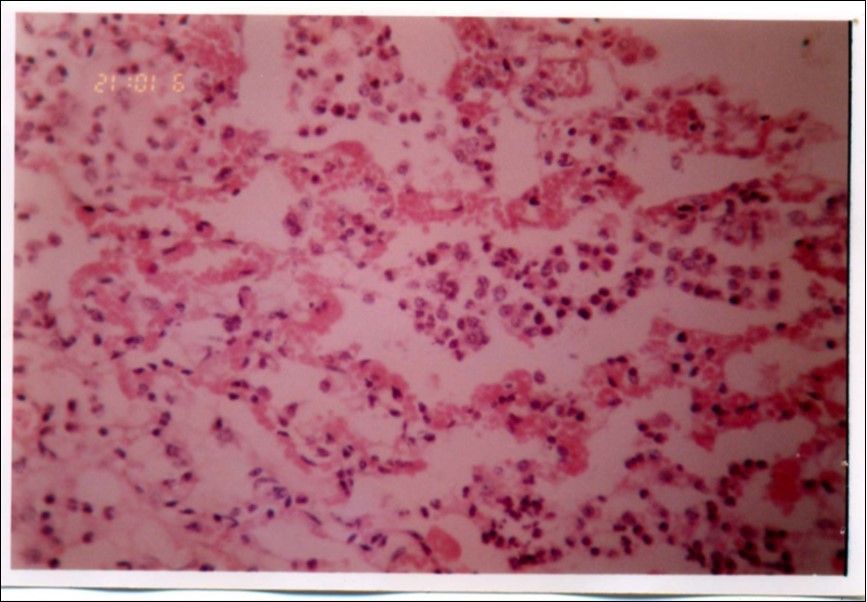

Figure 3, Figure 4 and Figure 5 show different histopathological pictures of hepatized lung tissue samples from which Mmm isolates were recovered. In Figure 3, widened interlobular septa, due to presence of fibrinous necrosis and cellular infiltration were observed. Figure 4 shows extensive loss of airspace due to necrosis and infiltration of neutrophils. Figure 5 shows hyperemia of alveolar wall capillaries and infiltration of few fibrin and neutrophils.

Figure 5.Hyperemia of alveolar wall capillaries, presence of few fibrin and neutrophils infiltration (H&E ×400).

Although no advanced techniques like PCR were used to identify the isolates, procedures used in this study were quite enough to confirm the incidence. Affected animals with CBPP were diagnosed based on the clinical signs, the PM findings, the typical histopathological picture in addition to the isolation of the causative agent and its subsequent identification using cultural and biochemical procedures. Identification of the isolates was confirmed by the growth inhibition test as recommended in OIE manual 10. The histopathological sections of diseased lungs, from which Mmm (SC) was isolated, showed typical histopathological picture of CBPP. The CBPP lesion comprises abronchiolar necrosis and oedema which progress rapidly to an exudative serofibrinous bronchiolitis with extension to the alveoli and uptake of alveolar fluid into tissue spaces 17, lymphatic vessels and ultimately septal lymphatics 18. With stasis, lymphatic vessels become thrombosed and ultimately fibrosed 19. The histological section of the lung in acute stage of the disease showed odema in the lymphatics of the interlobular septa and interstitial tissue and massive infiltration of fibrin, macrophage and neutrophils into the alveolar lumen 20. Also there was presence of lymphocytes and alveolar macrophages around the lymphatic vessels and septa margin 21. These findings supported the isolation results and gave additional evidence for the diagnosis of the disease.